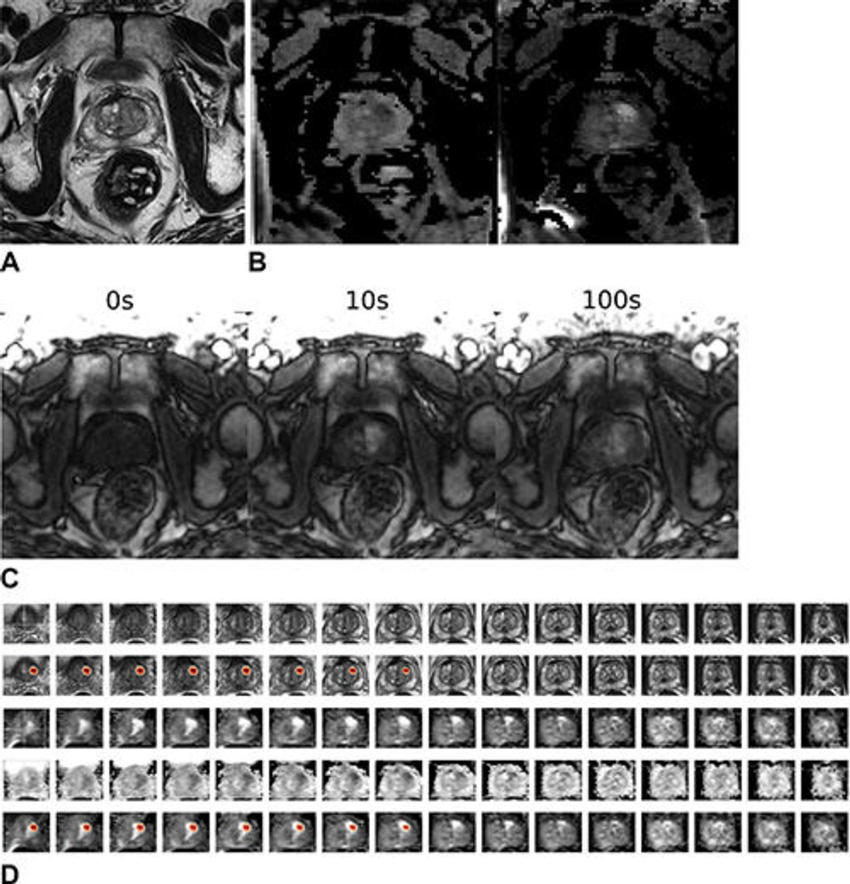

Figure 5. Images in a 59-year-old male patient who underwent MRI for clinical suspicion of prostate cancer (internal test set). The patient subsequently underwent prostatectomy and had a 1.5-cm prostate adenocarcinoma (Gleason score 3 + 4) in the right mid anterior to bilateral posterior inferior prostate gland. The model’s output (patient level probability) was 0.83. Only the lesion in the right lobe was highlighted by the gradient-weighted class activation map (Grad-CAM). The radiologist graded this examination as Prostate Imaging Reporting and Data System (PI-RADS) 4 for the right lobe lesion and PI-RADS 3 for the left lobe lesion. (A) T2-weighted image (representative section). (B) Apparent diffusion coefficient map (representative section, left) and high-b-value diffusion-weighted image (representative section, right). (C) T1 dynamic contrast-enhanced images (representative sections). (D) Volumetric composite of T2-weighted images (rows 1 and 2), diffusion-weighted images (rows 3 and 5), and apparent diffusion coefficient maps (row 4), with superimposed Grad-CAMs (rows 2 and 5). All images are in the transverse plane.